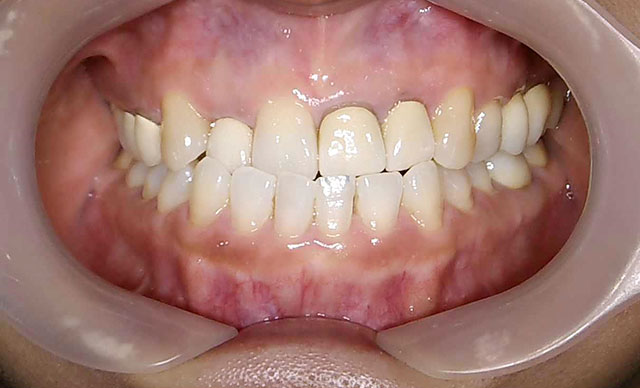

- case.9

術前

術後

症状:八重歯がでている治療期間約6ヶ月